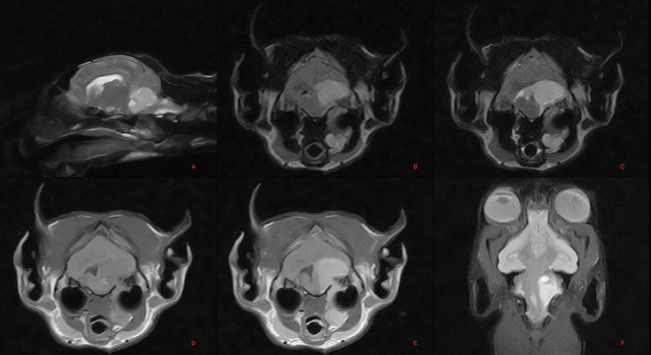

The images showed a voluminous extra-axial lesion, with irregular morphology and defined margins, affecting the region of the left metencephalon, with intracranial extension in the region of the pons, in the rostral portion of the medulla oblongata, in the cerebellar vermis, flocculus, and left cerebellar hemisphere (Fig. 1).

Erosion of the petrous portion of the left temporal bone was observed with extracranial extension and slight dorsal compression of the left tympanic bulla, which appeared slightly deformed. In addition, there was invasion/compression of the left longus colli muscle and digastric muscles.

The lesion signal appeared hyperintense to the brain parenchyma and surrounding musculature and heterogeneous in the T2-weighted, fluid-attenuated inversion recovery (FLAIR), STIR, and GET2* sequences, and isointense in the T1-weighted sequences. Contrast uptake was marked and heterogeneous.

The lesion resulted in compression and right dislocation of the pons, medulla oblongata, cerebellar vermis, and left cerebral hemisphere. It compressed and displaced to the right the mesencephalic aqueduct and rostrolaterally to the left, the left lateral recess of the fourth ventricle, which appeared slightly distended.

There was a slight symmetrical dilation of the entire ventricular system, including the cavities of the olfactory bulbs. Marked perilesional edema was present. The extracranial portion of the lesion caused mass effect and lateral dislocation of the left hemiportion of the hyoid bone.

Fig. 1. Magnetic resonance imaging (MRI) of the skull: T2-weighted images of the brain, parasagittal plane (A), STIR image, transverse plane at the level of the pons (B), T2 weighted image, transverse plane at the level of the pons (C), T1 weighted image, transverse plane at the level of the pons (D), T1 weighted post contrast image, transverse plane at the level of the pons (E). Dorsal Gradient Echo T2* weighted image of the brain, dorsal plane (F). Voluminous extra axial lesion affecting the region of the left metencephalon.